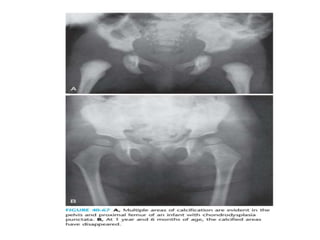

• Hallmark of the disease is the presence of multiple punctate

opacities(non specific) in the unossified cartilage at the ends

of the long bones, the tarsals, the pelvis, and the vertebrae.

• Early diagnosis is important because the characteristic

punctate calcifications disappear within the first year of life

• Hallmark ofthe disease is the presence of multiple punctate opacities(non specific) in the unossified cartilage at the ends of the long bones, the tarsals, the pelvis, and the vertebrae. • Early diagnosis is important because the characteristic punctate calcifications disappear within the first year of life • Peculiar appearance of a duplicate calcaneus (also in thanatophoric dysplasia)